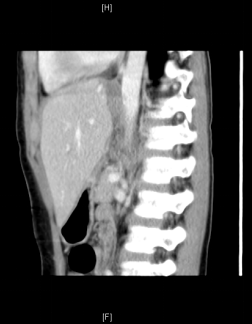

术前增强CT可见右肝巨大占位,约15x13x17cm,左肝推移,下腔静脉肝内段和中肝静脉受压,右肝静脉显示不清。